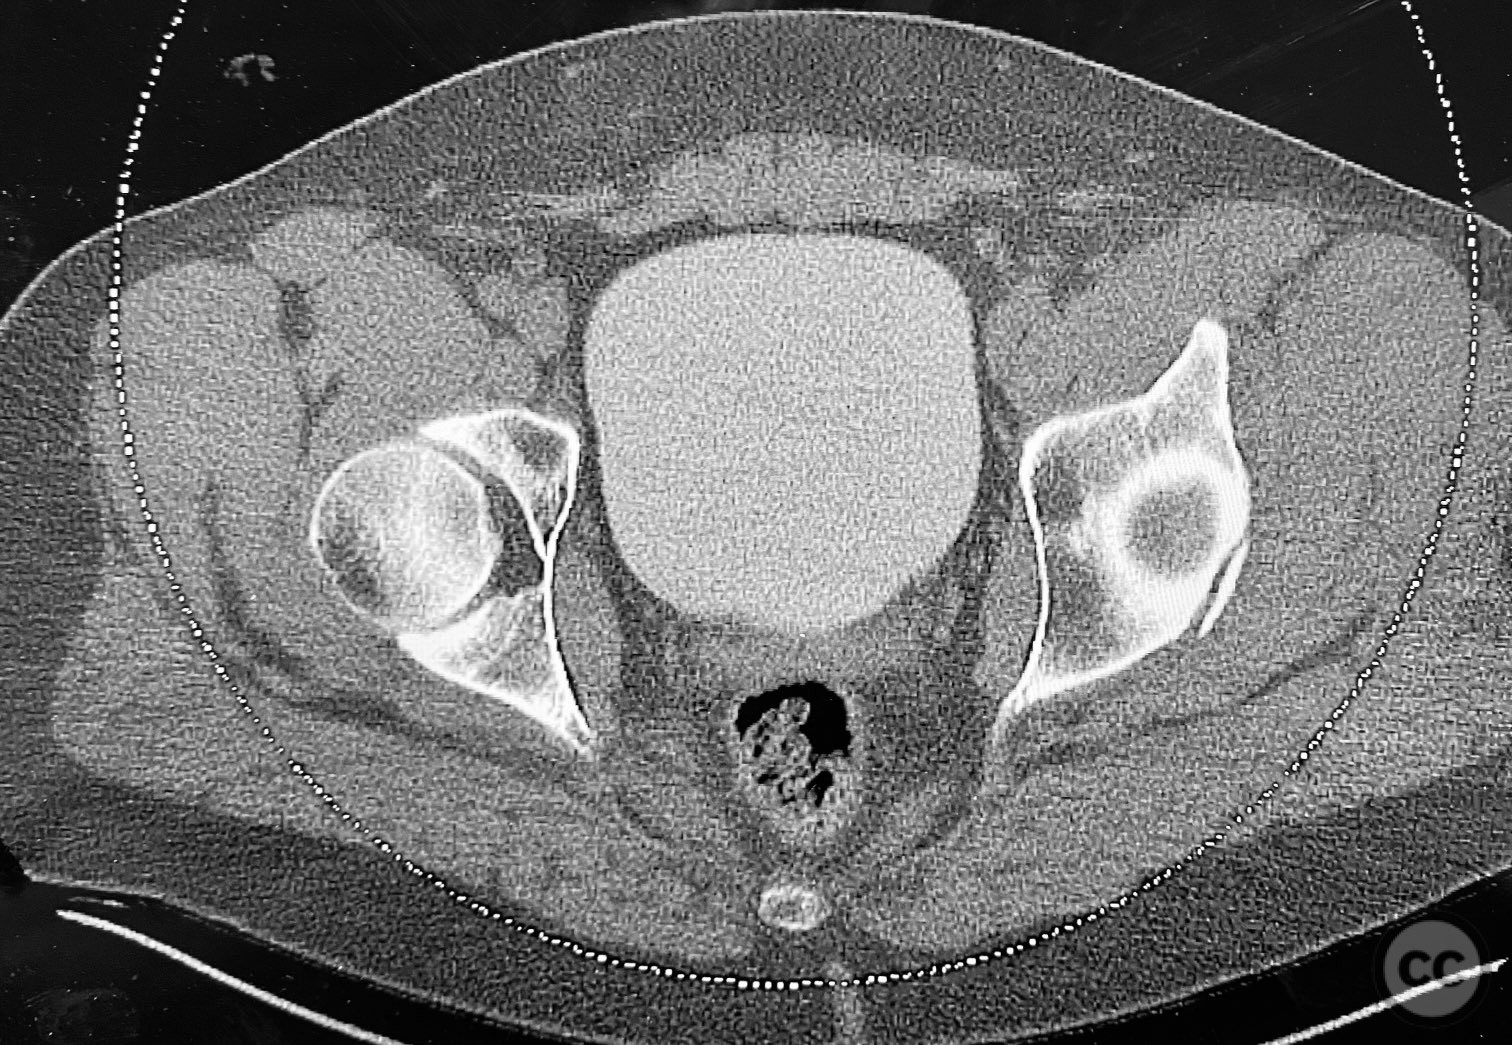

Acetabulum - AO/OTA 62x